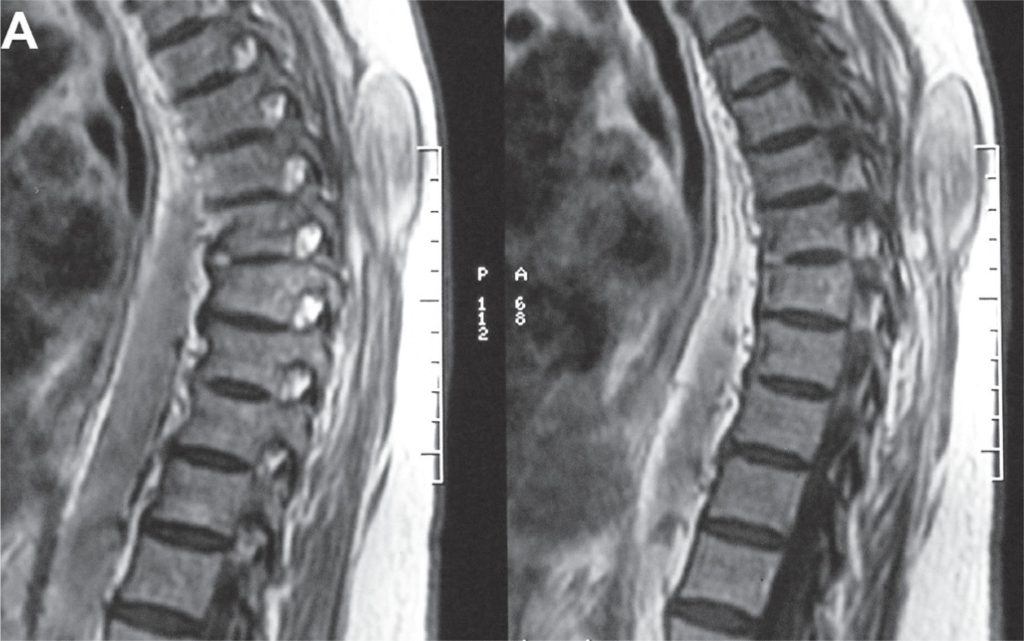

An 84-year-old Caucasian woman required a neurosurgery treatment for right T12-root neuroma after progressive paraparesia. However, 8 months after surgery, a non-pulsatile, and painless paravertebral swelling was observed. A magnetic resonance imaging showed on T1-weighted and T2-weighted examination a hyperintense right large paravertebral tumor. A well-limited paravertebral mass, not related to the central nervous system, was identified during the surgery. This tumor was completely excised and was defined as desmoid tumor. No personal or familial polyposis was characterized. The patient had a good outcome and died 3 years later due to other clinical complications.